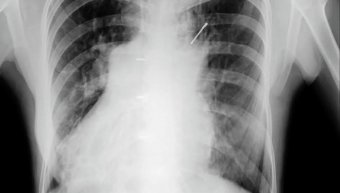

Έφθασαν οικογενειακώς στην κλινική Ζαφείρη με ακτινογραφία κοιλίας μικρού παιδιού αγοριού περίπου τεσσάρων χρόνων που είχε καταπιεί τρία καρφιά δεν θυμάμαι τα νούμερα οκτάρια ή εννιάρια και ήταν μέσα στο στομάχι.

Όταν τα παιδιά καταπίνουν κάποιο αντικείμενο εάν είναι στρογγυλό χωρίς μύτες και αιχμές ο ίδιος ο οργανισμός μπορεί να το αποβάλλει μαζί με τα κόπρανα όπως κέρματα και μπίλιες, αλλά τα καρφιά πρέπει άμεσα να γίνει χειρουργείο γιατί υπάρχει μεγάλος κίνδυνος να τρυπήσουν το στομάχι ή το έντερο.

Το χειρουργήσαμε με προσοχή με μία μικρή οπή στο στομάχι ίσα ίσα που να βγούν τα καρφιά και πήγαν όλα καλά δίχως μετεγχειρητικά προβλήματα .

Γι'αυτό χρειάζεται μεγάλη προσοχή στα μικρά παιδιά με το τί παιχνίδια παίζουν και μακριά από μικρά αντικείμενα που μπορούν να τα καταπίνουν όπως δείχνουν πολλές εικόνες από ακτινογραφίες το τί αντικείμενα υπάρχουν μέσα στο στομάχι αλλά και σ'όλο τον οισοφαγογαστρεντερικό σωλήνα.